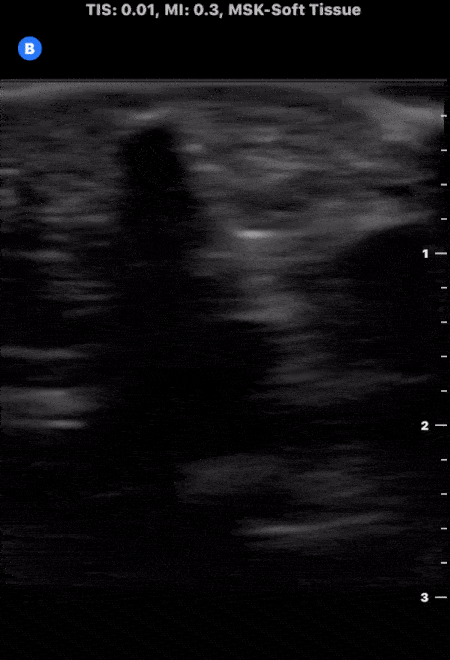

A patient presented to the emergency department following puncture by the tip of a palm frond. A puncture wound was noted with a palpable object under the skin. Soft tissue ultrasound was performed which demonstrated evidence of superficial foreign body as noted by the small hyperechoic structure with associated shadowing. The foreign body was successfully removed without issue. Image courtesy of The POCUS Atlas Team